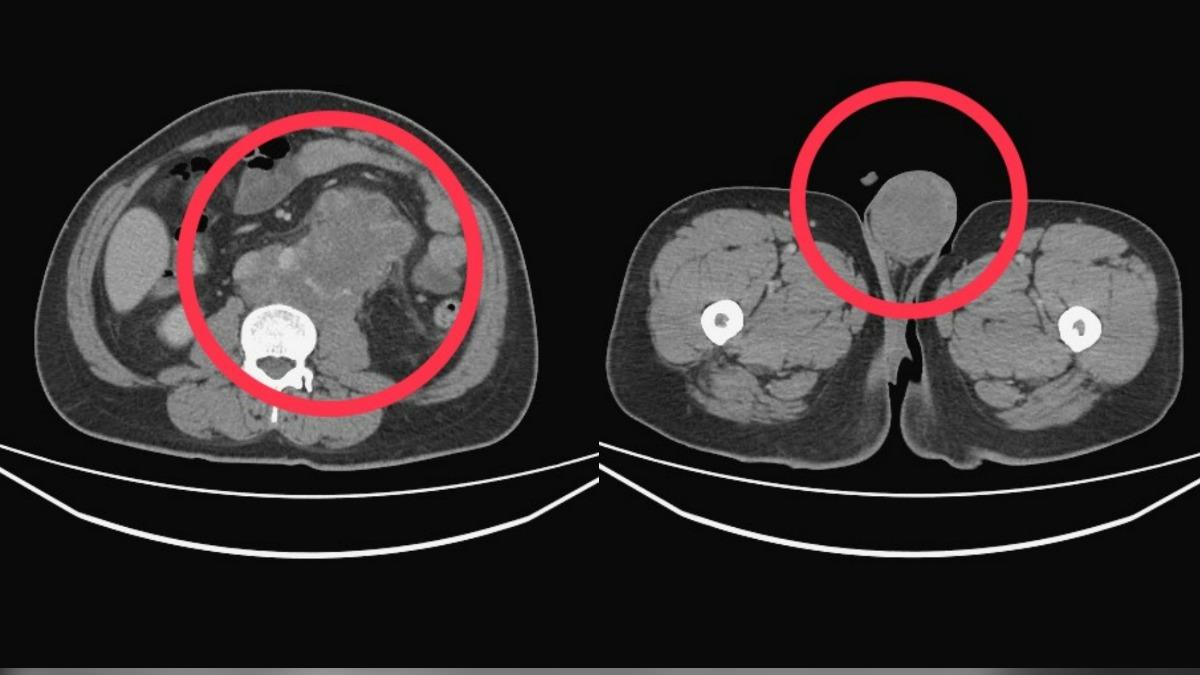

收治個案的衛生福利部台中醫院血液腫瘤科主治醫師江佳駿表示,患者身材壯碩,自恃年輕體健,但入院時出現咳血、甚至坐著也喘不過氣的狀況,X光及電腦斷層掃描檢查,結果發現,體內已經滿是腫瘤,塞滿肺臟、肝臟及後腹腔。

江佳駿表示,醫療團隊隨即展開緊急治療,但患者的病程進展極其迅速且凶猛,兩週內,患者肺部的腫瘤就從半滿惡化至全滿,患者在確診一個多月後,就因多重器官衰竭不幸離世。